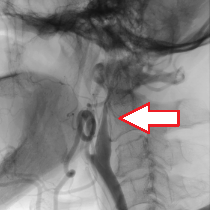

(下図)内頸動脈狭窄症に対して頸動脈ステント留置術を施行しました。良好な拡張が得られています。

頸動脈狭窄症、〇が狭窄している部分

頸動脈ステント留置術後

頸動脈狭窄症

脳梗塞の原因となります。外科的治療では、直接血管を切開して動脈硬化の部分を取り除く頸動脈内膜剥離術(CEA)が行われます。血管内治療では、動脈硬化による狭い部分にステント(金網でできた筒)を送り込んで拡張する頸動脈ステント留置術(CAS)が行われます。